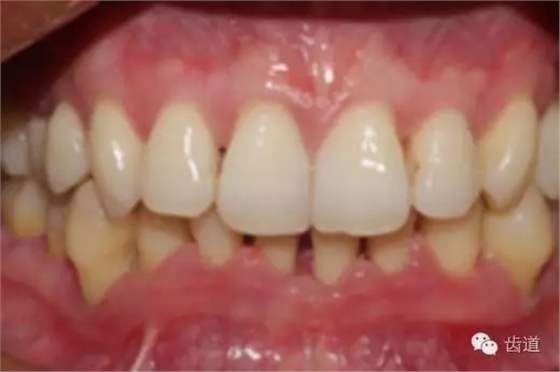

2、牙齦

(顏色、形狀、質地、退縮、BOP、PD、附著齦)